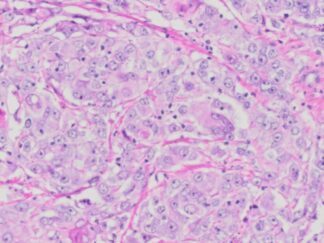

Human Breast Cancer FFPE Sections

VitroVivo Biotech provide human breast cancer FFPE sections with ER,PR and HER2 data. These sections are mounted on positively charged glass slides and sectioned at 5 µm thickness. These FFPE slides can be used to perform RNA scope ISH, FISH IF, IHC and NGS, etc.